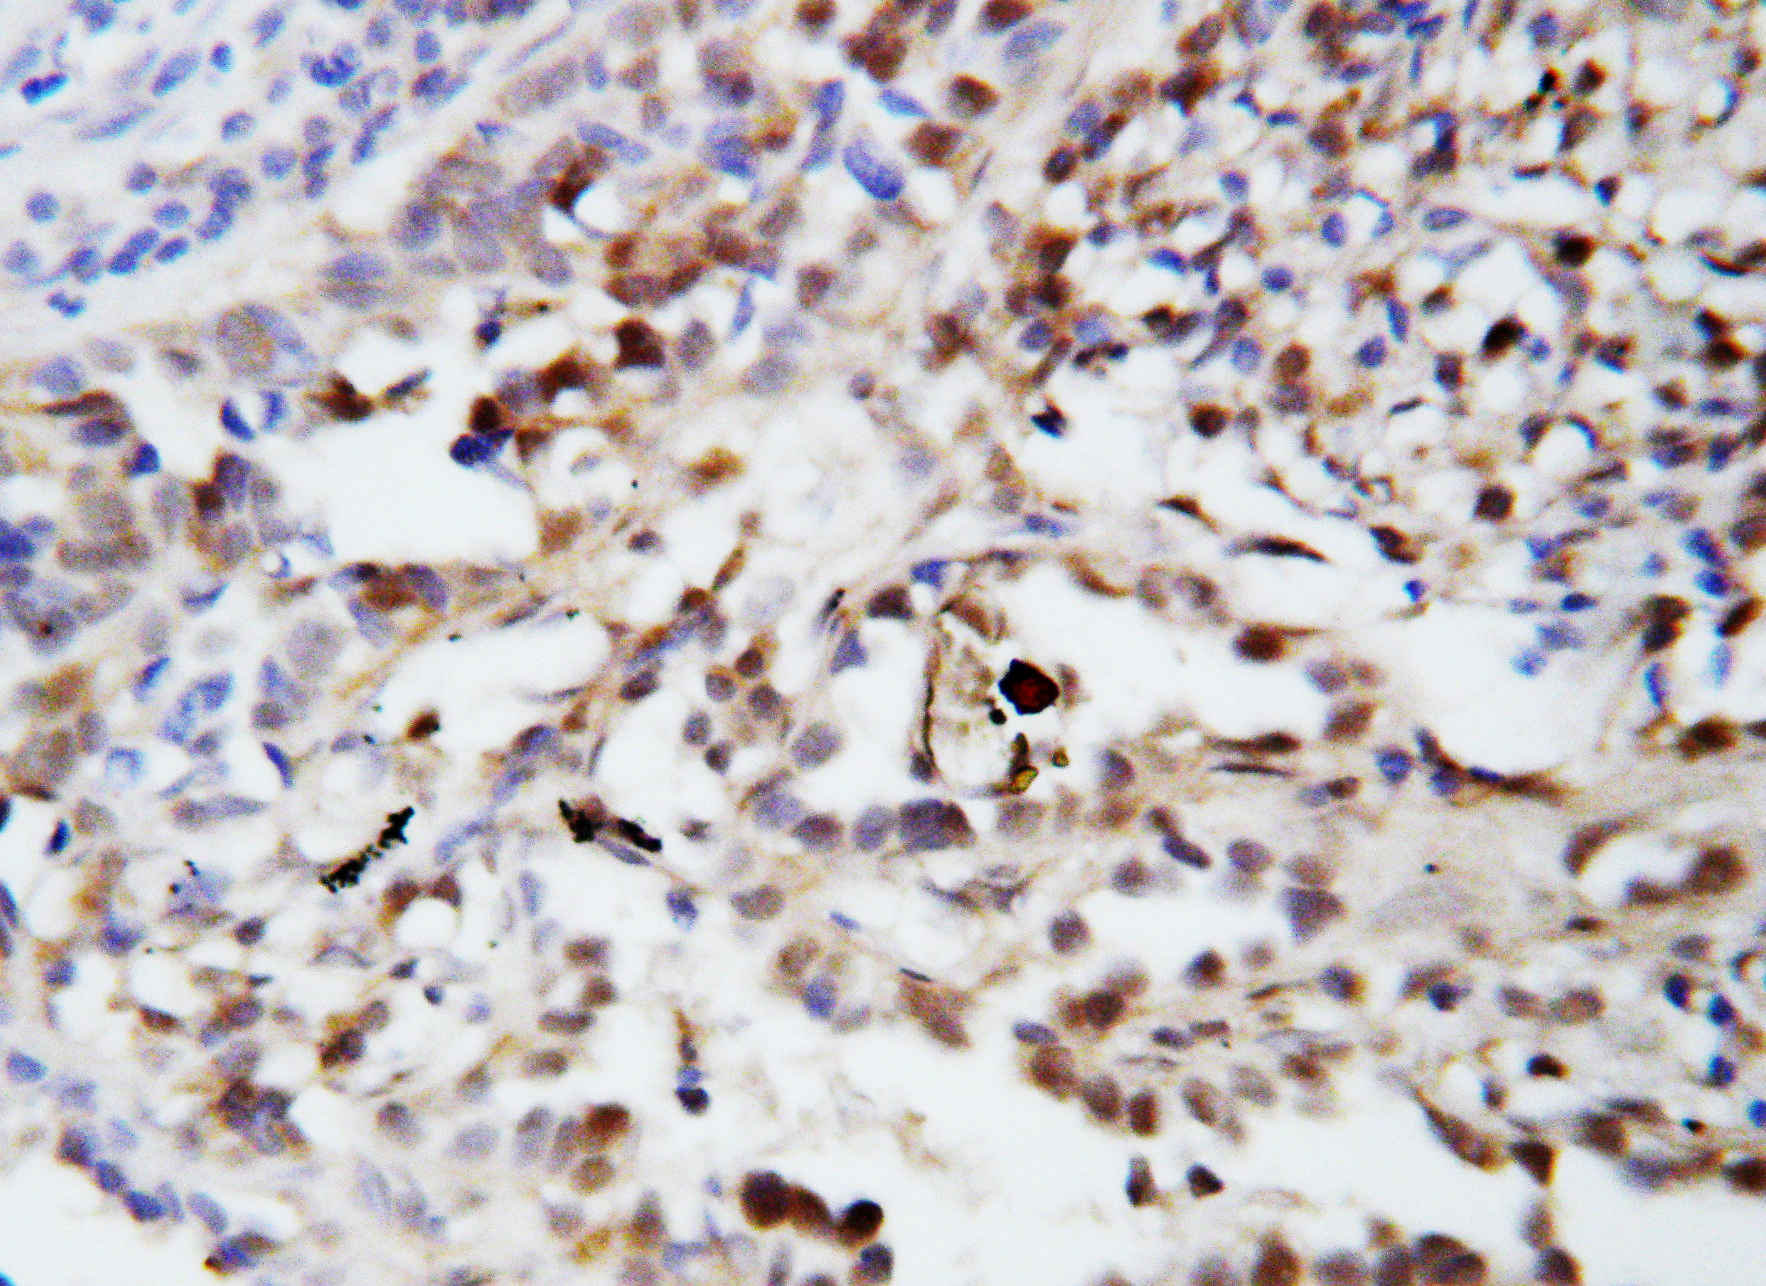

IHC analysis of Ubiquitin/UBB using anti-Ubiquitin/UBB antibody (BA3363-2).

Ubiquitin/UBB was detected in a paraffin-embedded section of human lung cancer tissue. The tissue section was incubated with rabbit anti-Ubiquitin/UBB Antibody (BA3363-2) at a dilution of 1:200 and developed using HRP Conjugated Rabbit IgG Super Vision Assay Kit (Catalog # SV0002) with DAB (Catalog # AR1027) as the chromogen.